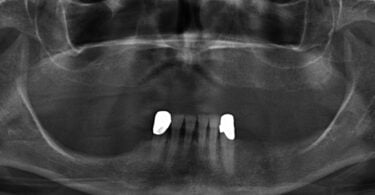

Quatro dos seis implantes foram de 5,5 mm de comprimento por 5 mm de diâmetro, um implante foi de 6,5 mm de comprimento por 3,75 mm de diâmetro e o último implante foi de 6,5 mm de comprimento por 5 mm de diâmetro (figura 2).

As seguintes imagens apresentam um dos casos incluídos no estudo (figura 03 – 15).